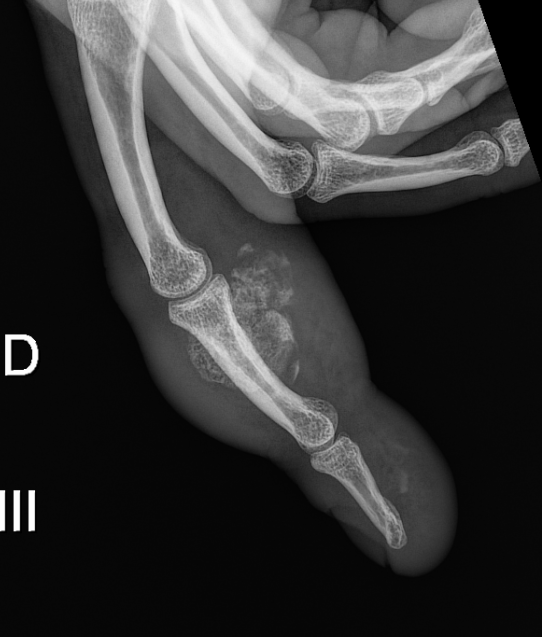

Need help with this finger case ( NORA ?)

30 Y O man Growing lump . I think about a NORA tumor as my first differential . Any other ideas.

Bizarre parosteal osteochondromatous proliferation (BPOP)/Nora´s lesion. I think it's the most likely diagnosis. Other options may include parosteal osteosarcoma or CPDD, anyways I think they are less probable